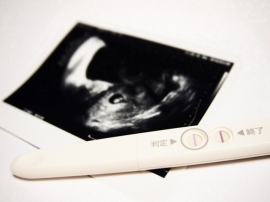

新型出生前診断は、妊婦の血液からダウン症など3種類の染色体異常を調べることができ、新型出生前診断の臨床研究を実施している病院グループの発表よると、導入から3年間で計3万615人が検査を受け、1.8%にあたる547人が陽性と診断された。[写真拡大]

従来の出生前診断は、穿刺法で母体を傷つけて流産のリスクを伴う問題があったが、新型出生前診断はわずか20ccほどの血液を注射器で採取するだけであり、母体への負担を大幅に軽減できる。

新型出生前診断は、妊婦の血液からダウン症など3種類の染色体異常を調べることができ、新型出生前診断の臨床研究を実施している病院グループの発表よると、導入から3年間で計3万615人が検査を受け、1.8%にあたる547人が陽性と診断された。

ただ、誤解されがちだが、新型出生前診断はすべての先天性異常を出産前に発見できるわけではない。新型出生前診断は、13トリソミー、18トリソミー、ダウン症候群の可能性を高い精度で予見する検査であり、それ以外の先天性疾患を調べたいとなると、羊水検査などの検査が必要になる。

また、3つの染色体異常についても、確実に見抜けるわけではない。検査結果が陰性であっても、ダウン症候群を患っていないという保証はないのだ。検査の時期についても、妊娠10~18周期の時期でなければ受けることができない。日本産科婦人科学会が2012年にまとめた指針では、対象者は「超音波検査などで胎児の染色体異常の可能性が示唆された妊婦や高齢妊婦」とされている。費用は健康保険が適応されず、自費で20万円程度。「母体血を用いた出生前遺伝学的検査」の認定施設は2016年6月時点で70施設ある。

集計によると、新型出生前診断で陽性と判定され、羊水検査を受けた458人のうち91%にあたる417人が染色体異常と診断されたという。そのうち94%にあたる394人が人工妊娠中絶を選択した。

一方、陽性と判定されたうち89人は羊水検査を受けておらず、多くは死産だとみられ、89人中13人は研究から離脱して人工妊娠中絶を選んだケースもあるとみられている。

病院グループ事務局の関沢明彦・昭和大教授は、94%が中絶を選択したことを受け、「当事者たちは悩んで苦渋の決断をしている。最終的な判断は尊重されるべきだと考える」と述べた。(編集担当:久保田雄城)